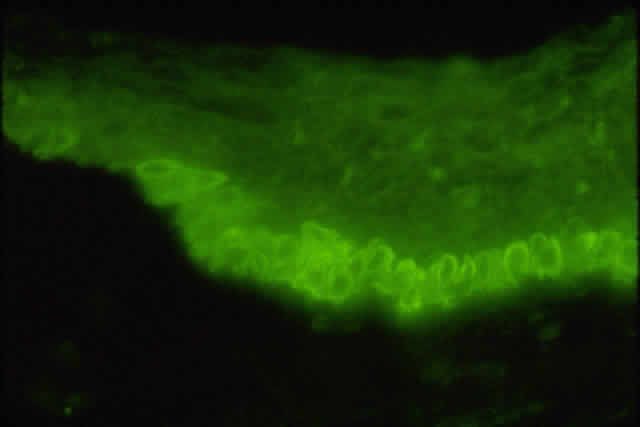

Ultrastructural studies of goblet cells suggest an apocrine secretory mechanism that releases mucus in the form of packets; however, this has not been demonstrated conclusively (Fig. 14A and B).50 This secreted mucus forms the posterior layer of the tear film. Other layers of the tear film include an aqueous layer containing soluble proteins and mucins and a thin anterior layer consisting of meibomian gland oil.51 Mucus is released rapidly in response to surface irritants, trauma, or toxins. This reflexive response is necessary to replenish the mucous layer and to protect the ocular surface. Recent evidence indicates that parasympathetic and sympathetic nerves are located adjacent to the goblet cells. It is not clear whether the cells are directly innervated (Figs. 15 and 16).52,53 However, corneal debridement causes goblet cell secretion,54 suggesting that ocular damage stimulates the reflex sensory nerves of the cornea to activate a local reflex arc. In turn, the efferent neurons in the conjunctiva activate and release neurotransmitters, which stimulate the goblet cells. This is supported by the fact that topical application of vasoactive intestinal peptide (VIP), serotonin, epinephrine, dopamine, or phenylephrine stimulates conjunctival goblet cell mucus secretions.52,54

Fig. 16. Fluorescence micrograph of section from inferior conjunctiva showing tyrosine hydroxylase (TH)-containing nerve fibers. Presence of TH indicates that sympathetic nerve fibers surround individual goblet cells. (Original magnification; × 600. Dartt DA, McCarthy DM, Mercer HJ et al: Localization of nerves adjacent to goblet cells in rat conjunctiva. Curr Eye Res 14:993, 1995)